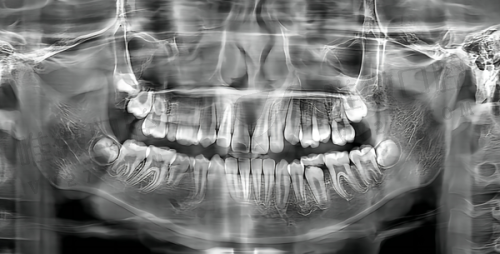

不少人反?。骸笆跚耙缴嶂苯釉?D影像上画图教你看,说得直白又生动;术后哪怕是周六晚上十点也有人微信问你酸胀有没有缓解?!?/p>